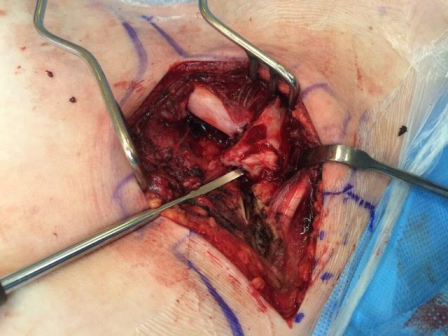

Fig. 1: X-ray chest showing both clavicles

A 15-year-old boy was hit on his right shoulder, while playing football. Physical examination showed pain, swelling and deformity of the left SC area and of the medial fourth of the clavicle. Hollow area was felt next to the right sternoclavicular joint. Neurovascular examination was normal and there was no sign of dysphagia or dyspnea.

Right sternoclavicular dislocation with fracture of the medial end of clavicle.